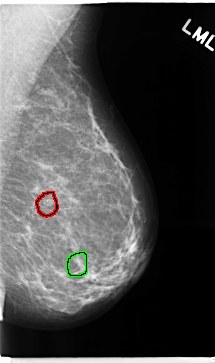

C_0271_1.LEFT_MLO

LEFT_MLO LINES 4712 PIXELS_PER_LINE 2784 BITS_PER_PIXEL 12 RESOLUTION 50 OVERLAY

FILE: C_0271_1.LEFT_MLO.OVERLAY

TOTAL_ABNORMALITIES 2

ABNORMALITY 1

LESION_TYPE CALCIFICATION TYPE PUNCTATE DISTRIBUTION CLUSTERED

ASSESSMENT 3

SUBTLETY 4

PATHOLOGY BENIGN

TOTAL_OUTLINES 1

ABNORMALITY 2

ASSESSMENT 4

SUBTLETY 5